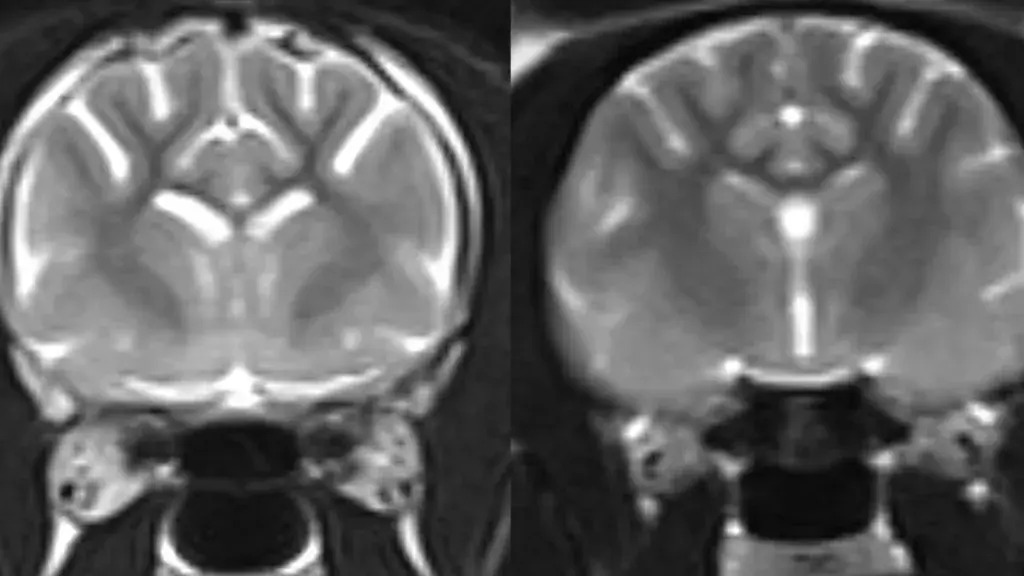

Foto: Universidade de Edimburgo

As áreas claras na imagem de ressonância magnética à esquerda, relativa a um gato vivo com demência, mostram mais perda de tecido cerebral em comparação com as da imagem direita, relativa a um cérebro felino normal.